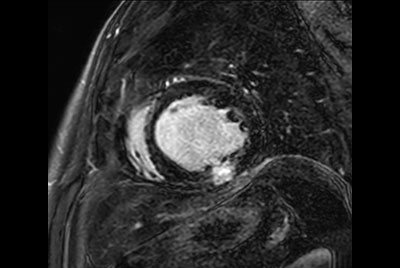

Shoulder with oncologic mass